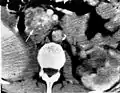

Pancreatic serous cystadenoma is a tumour of the pancreas.[2][3] It is typically noncancerous, solitary, and found when investigating something else.[3] One third of pancreatic cysts are serous cystadenomas.[3]

It is usually found in the body or tail of the pancreas, and may be associated with von Hippel–Lindau syndrome.[3]